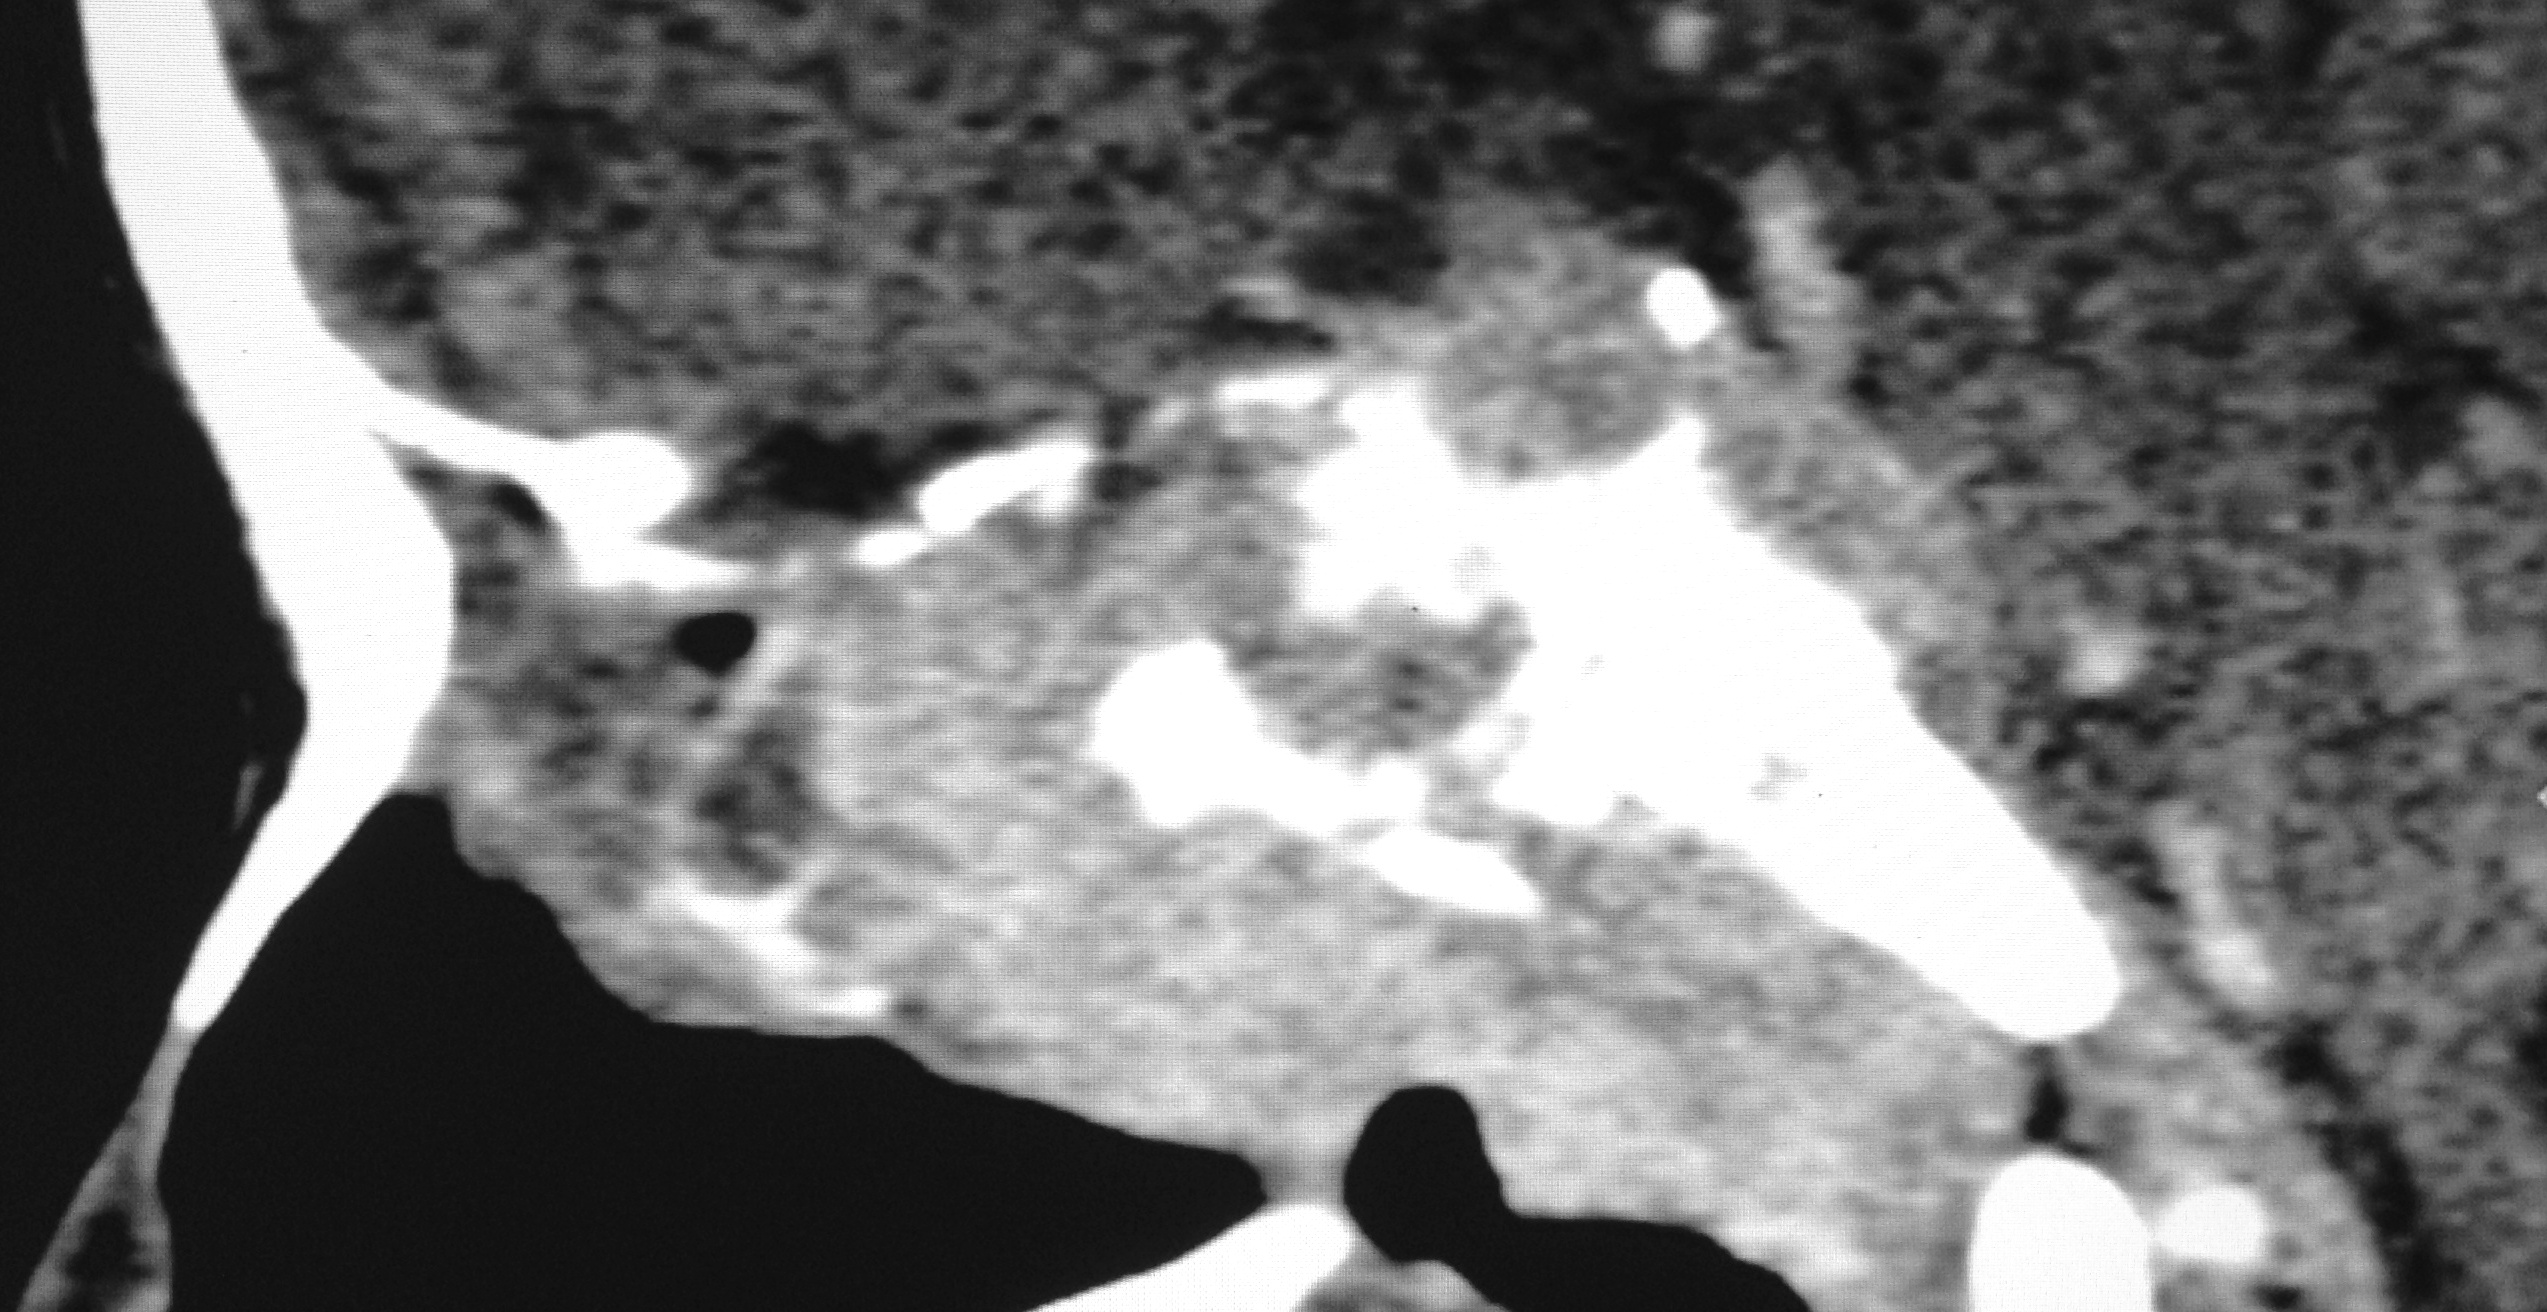

Nasopharyngeal carcinoma is a malignant disease and is more common in males than in females with M:F ratio of 3:1. It has a bimodal peak at 16-20 and 46-50 years of age. Orbital involvement is seen in 3.2% and bilateral orbital invasion occurs in 0.7% of patients with nasopharyngeal carcinoma. Imaging has significant role in detecting the early nasopharyngeal carcinoma, tumor staging, involvement of lymph node, monitoring the patients after the therapy, to detect recurrence and radiation associated changes in the soft tissue and bone. We report a case of aggressive nasopharyngeal carcinoma in 22 years old male who presented with rapidly progressive diminution of vision.